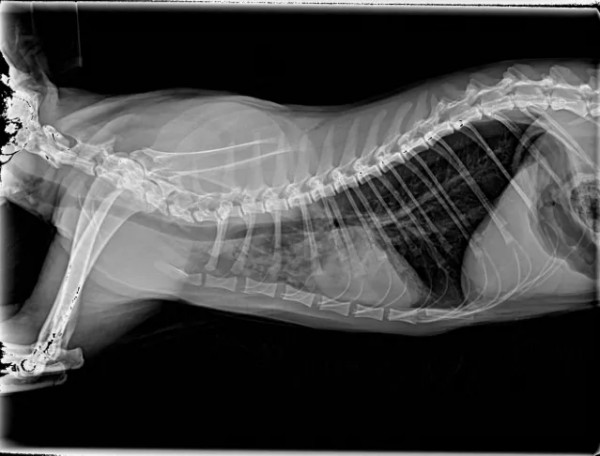

一、引言 猫咪肺炎根据发病快慢有急性肺炎和慢性肺炎之分,猫咪急性肺炎的症状主要表现为突然发高烧、呼吸不畅、腹泻等;慢性肺炎通常表现为长时间咳嗽、有痰、食欲下降、精神不振、呼吸不畅等。 猫咪如果患上肺炎就需要及时治疗,否则很容易引发相关的并发症,威胁到猫咪的性命。肺炎常见原因:感染性(细菌感染、病毒感染、寄生虫感染)、非感染性(吸入性、异物性、过敏性、继发性等) 二、病例基本信息及病史 2.1基本信息 一只缅因猫,雄性未绝育,体重5.85Kg,免疫不全,驱虫正常。 2.2主诉疾病史 最近几天精神良好,就诊当天发蔫,食欲不振,偶尔咳嗽,打喷嚏,4天前家里新领养一只小猫。既往病史 :疱疹病毒,杯状病毒,伯氏杆菌。 三、检查及化验项目和结果 3.1血常规检查 3.2 血清样淀粉蛋白检查 3.3生化检查 3.4fNT-PrOBNP猫N端脑钠肽前体 3.5影像学检查 四、诊断结果 肺炎;肺叶实变 五、治疗方案及预后 5.1经验性治疗 克维舒:一天两次,一次2ml; PO 麻杏石甘汤:一天两次,一5ml;PO 5.2复诊 用药2周后复诊,整体情况好转,咳嗽明显好转,喷嚏减少,分泌物减少,食欲恢复。炎症指标明显好转,肺部影像明显好转。 5.3复查结果 5.3.1血常规检查 5.3.2 血清样淀粉蛋白检查 5.3.3影像学检查 图4胸腔侧位 5.4治疗转归 巩固治疗:克维舒 一天两次,一次2ml,PO 该动物目前恢复良好,状态稳定,直至投稿前回访,一切正常。肺实变位置需密切监测,病变位置可能伴随终身。 六、讨论及小结 猫咪肺炎的发病原因一般是由细菌、真菌、病毒等微生物感染引起。甚至像寄生虫移行、外力因素、吸入性因素、机体免疫力下降等,都可诱发肺炎。严重的肺炎可能会导致肺部渗出增多、肺水肿等,引起急性呼吸困难。猫咪的肺炎在初期通常很隐蔽,甚至没有太大的症状和表现,发病非常突然,以精神沉郁、厌食、急性的呼吸困难为主,送医不及时容易耽误病情。该病例因为发现较早,治疗后整体预后良好。 肺炎的诊断:咳嗽的犬猫出现发烧、嗜睡、食欲不振或呼吸急促症状时应进行全面检查,血细胞计数和胸部X线检查评估是否存在肺炎。根据结果怀疑细菌性或支持细菌性肺炎的诊断时,应采集气管,支气管内或支气管肺泡灌洗进行细胞学检查,需氧培养、药敏实验和支原体培养。该病例未做相关检查,主人要求先对症治疗。 在开始抗菌治疗之前,都应该建议宠主进行培养和药敏实验,前提时动物状况足够稳定。但所有治疗检查应和宠主充分沟通,特别时需要长时间或管理时间比较长的病例,在治疗时应制定个性化治疗方案,将宠物主人的意愿,配合程度,可自由支配时间,动物配合程度都应纳入考量,从而提高治疗质量,护理质量以及医从性。 该病例综合考虑最终抗菌药物选用克维舒,一方面该病例未做培养及药敏,作为临床医生应选择一线广谱抗菌药物,安全性高的药物,从而提高治愈率。另一方面考虑到动物主人时间以及该猫吃药困难,克维舒易口服,操作简单,很大程度上减少猫咪应激,节省主人时间,同时增加了宠主成就感。从而提高了治愈率,也增加了宠主对医生的信任,所以最终选择了克维舒。 七、参考文献 1.Sykes, J. E. (2014).Feline lower respiratory tract disease. In J. E. Sykes (Ed.), Canine and Feline Infectious Diseases (pp. 161-173). 2.Reinero, C. R. (2011).Feline Asthma and Bronchopulmonary Disease. Veterinary Clinics of North America: Small Animal Practice, 41(2), 191–211. 3.Lappin, M. R., Blondeau, J., Boothe, D., Breitschwerdt, E. B., Guardabassi, L., Lloyd, D. H., ... & Sykes, J. E. (2017).Antimicrobial use Guidelines for Treatment of Respiratory Tract Disease in Dogs and Cats: Antimicrobial Guidelines Working Group of the International Society for Companion Animal Infectious Diseases. Journal of Veterinary Internal Medicine, 31(2), 279–294. 4.夏兆飞,陈艳云,王姜维主译.小动物内科学(第5版) [M].中国农业大学出版社,2019,11:297-300.